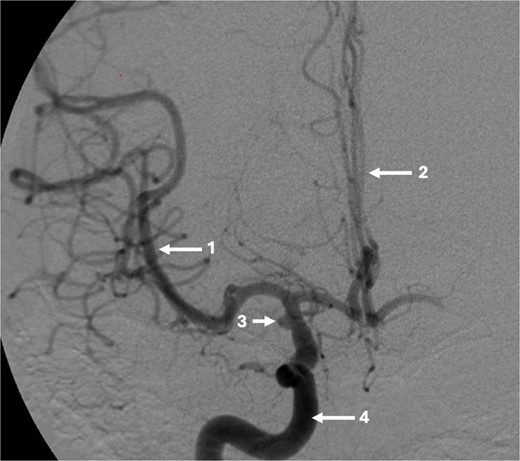

The DSA showed significant narrowing of the ACA and complete occlusion of the MCA distal to the clipped and fully occluded aneurysm. The right recurrent artery of Heubner, arising from A1, was hypertrophied and supplying the medial lenticulostriate territory. There was diffuse small vessel formation in this same area (Fig. 3). This DSA suggested the progressive distal stenosis secondary to the surgical clip led to anastomotic collateral formation, consistent with a radiological and clinical Moyamoya phenomenon. Patient’s symptoms were managed conservatively. Subsequent CT angiogram in 2018, 2021, and 2023 showed no further progression of the Moyamoya phenomenon.

Sagittal DSA demonstrating (1) Clip is in position across the terminal carotid. The frontal branch of the right MCA is supplied by collaterals from the (2) right ophthalmic artery (hypertrophied recurrent meningeal artery), right middle meningeal artery and right superficial temporal artery (via craniotomy site as pial synangiogenesis). There is collateral vessel formation consistent with Moyamoya phenomenon (4). (3) ICA. The A1 is not opacified likely due to the anterior communicating (ACOM) collateralisation.